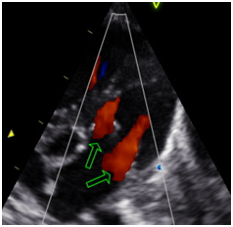

Usually they associated with aortic aneurysm, bicuspid aortic valve, aortic coarctation, subaortic stenosis, patent ductus arteriosus, abnormal interatrial and interventricular septum. They may evolve failure and / or mitral stenosis. (Figures 1–4)

Figure 4 Long Axis 5 cameras. Double mitral apparatus. Mitral presence of two flows.

Echocardiography is essential for the diagnosis, treatment and follow-up.4–5 We present a newborn preterm, low birth weight, the doppler echocardiogram applying for breath. echodopplercardiogram is performed evidencing patent foramen ovale with shunt from left to right, moderate muscle septal shunt left to nonsignificant right, double mitral apparatus, permeable, no records diastolic gradient and mild impairment of both, patent ductus arteriosus, big, not restrictive and overactive.